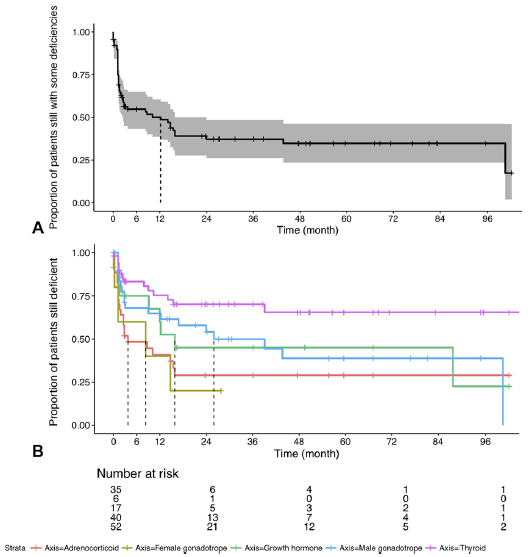

19. 内窥镜经蝶窦手术治疗后的非功能性垂体大腺瘤患者内分泌功能及腺体容积研究

Endocrine function and gland volume after endoscopic transsphenoidal surgery for nonfunctional pituitary macroadenomas

Author: Maya Harary, Aislyn C. DiRisio, Hassan Y. Dawood, John Kim, Nayan Lamba, Charles H. Cho, Timothy R. Smith, Hasan A. Zaidi and Edward R. Laws Jr.

DOI: https://doi.org/10.3171/2018.5.JNS181054

非功能性垂体腺瘤(NFPA)所导致的垂体功能丧失,可能是由于垂体受到压迫所致。有学者提出,腺体的大小和围手术期腺体的相对扩张可能与垂体功能的恢复有关,但影响程度尚不清楚。这项研究的目的是评估NFPA经蝶窦切除术后激素的变化情况,以及垂体扩张与内分泌恢复的关系。

本研究选择经蝶窦内窥镜手术切除非功能性大腺瘤的患者作为研究对象,而将既往有脑垂体手术或放疗的患者被排除在外。研究人员通过填写的表格信息获取患者特征和内分泌功能信息。采用长期MRI对术前和术后(≥6个月)垂体容积进行评估,从而研究内分泌功能随时间变化与临床特征(包括腺体体积)之间的关系。

在160例符合条件的患者中,47.5%为女性,而56.9%的患者术前垂体前叶激素存在缺乏。术前中位肿瘤直径及腺体体积分别为22.5mm和0.18cm³。在55%的患者中,经过为期24.4个月的中位数临床随访期,他们的内分泌功能恢复正常或得到改善。研究表明,年龄、性别、肿瘤大小与内分泌恢复的可能性存在相关性,患者的平均恢复时间为12.2个月,而甲状腺功能减退症的患者的恢复最慢。虽然腺体从术前到术后明显地重新扩张,但这与内分泌功能改善并无相关性。

内分泌功能的恢复可能需要手术后几个月甚至几年的持续时间,而有超过50%的患者表现出改善或正常的功能。维持或恢复患者的内分泌功能与肿瘤大小有关,而与腺体体积无关。

图:kaplan meier曲线显示,甲状腺功能减退与肾上腺机能不全和性腺功能减退相比,恢复速度较慢。

【张继】